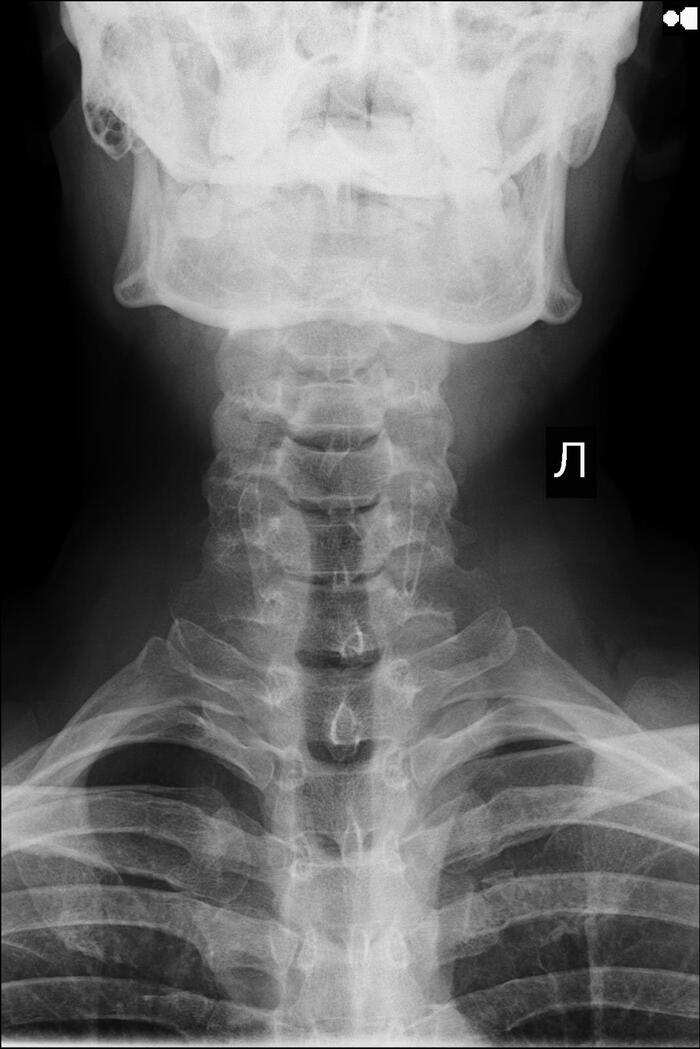

Ответ на пост «Найдены рентгеновские снимки древнего человека, который не чистил зубы и закусывал пиво сухариками»⁠⁠

Что на снимке не так?